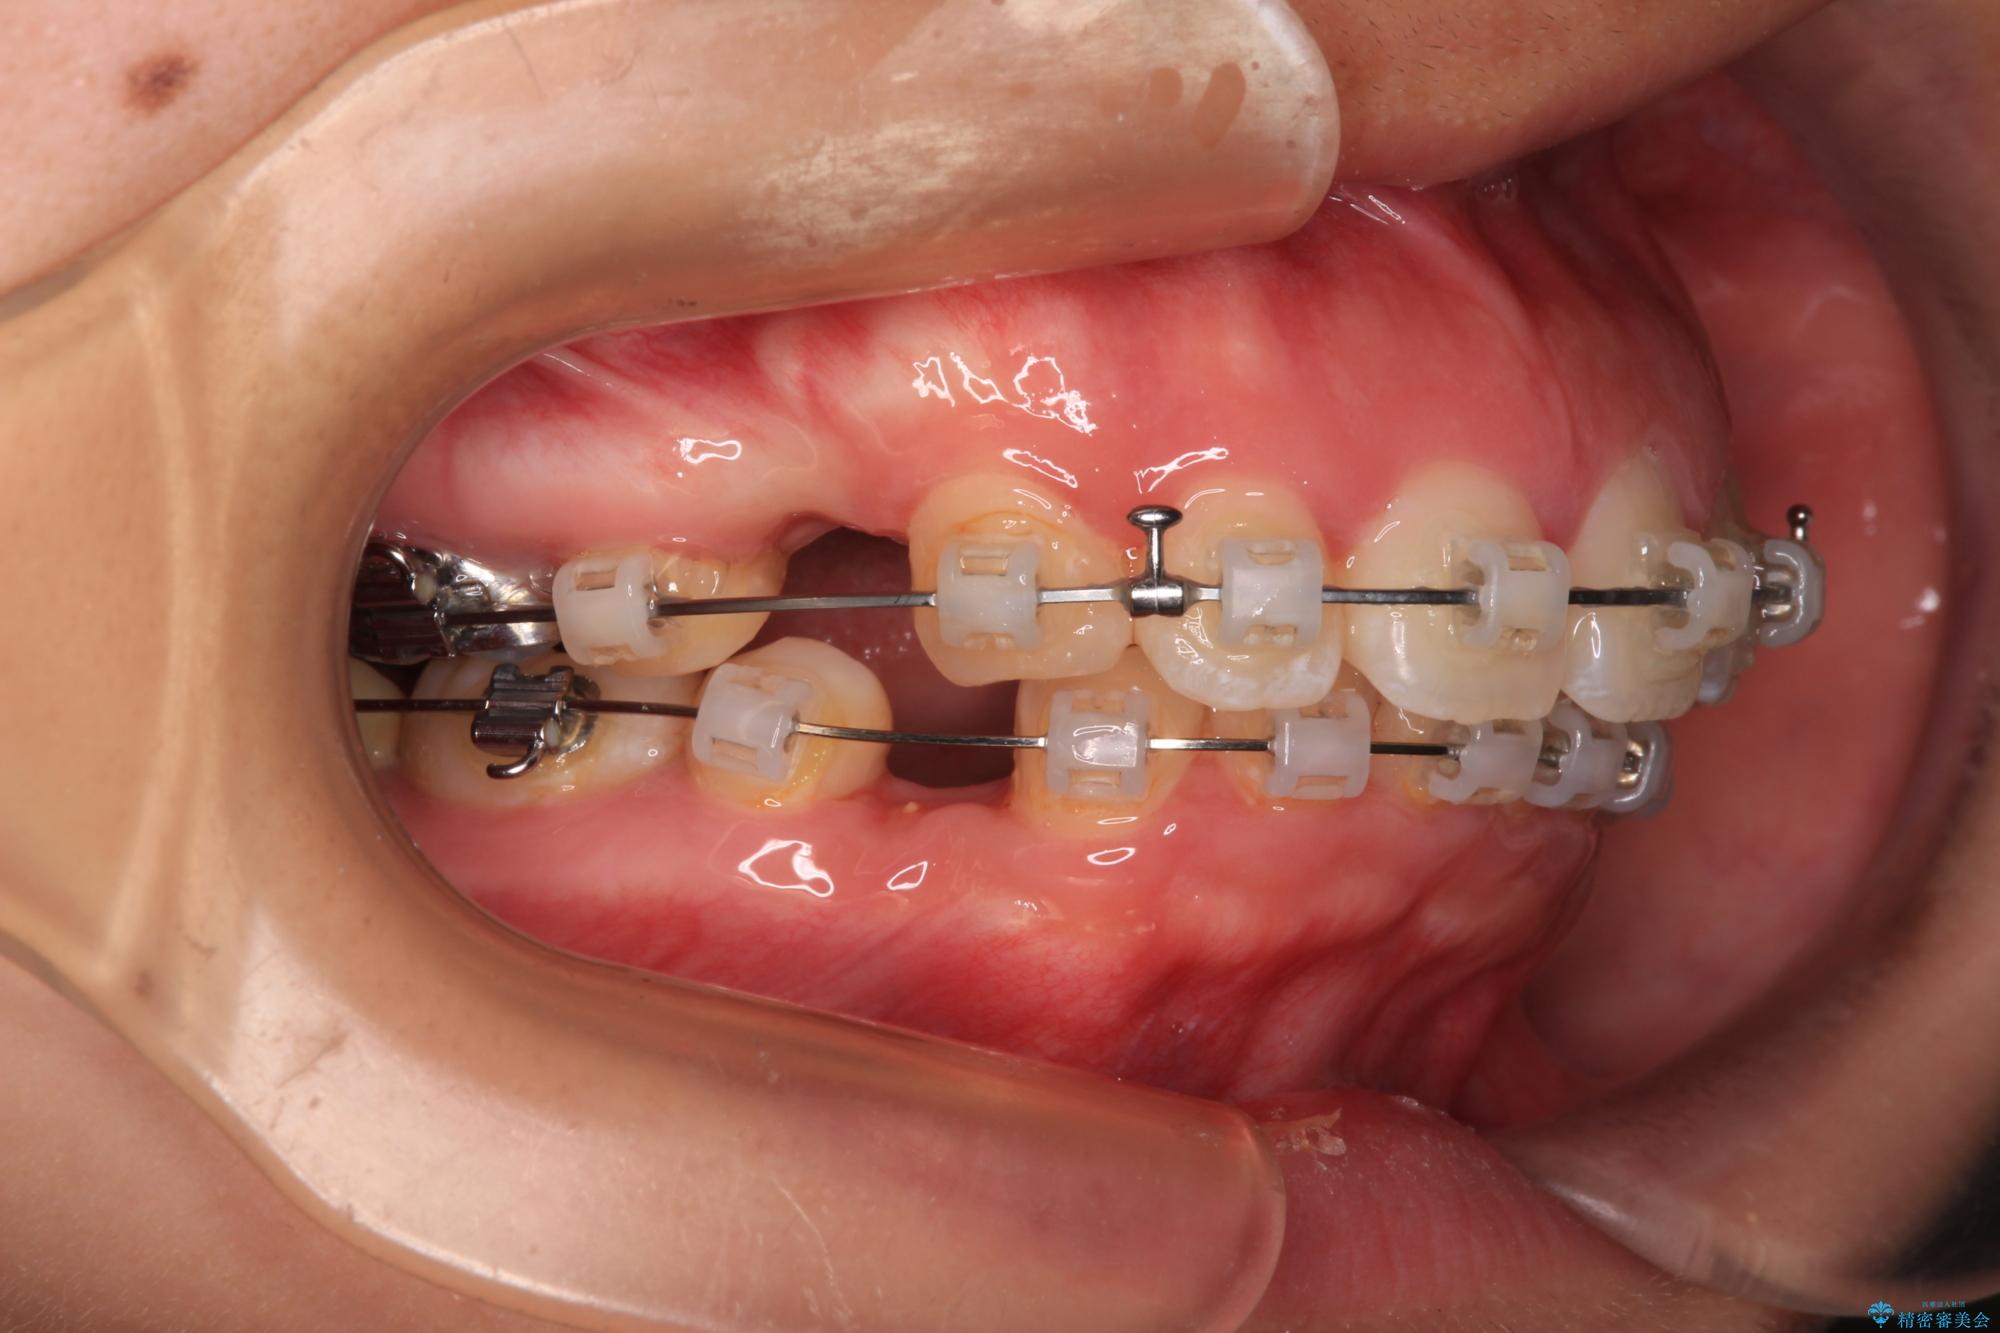

- 矯正装置

- クリアブラケット

また、上顎歯列が下顎に対して前方位に位置していたため、補助装置を用いて上顎歯列を後方に移動させ、より積極的に口元を下げるようにしました。

上下正中位置を改善するため、左下はイレギュラーに第二小臼歯を抜歯しました。そのため治療期間の長期化が予想されましたが、2年半ほどで期待通りの歯列に仕上げることができました。